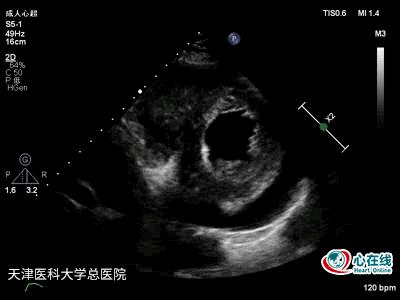

图2. 二维胸骨旁左心室短轴切面乳头肌水平示右心室增大,其内可见一不规则中等回声团块,活动度小,与心肌分界不清,右心室游离壁运动减弱,左心内径及室壁运动正常,心包腔内可见液性暗区,以后左心包腔为著。